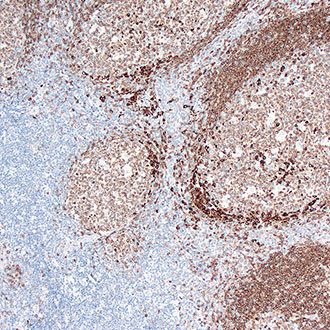

bcl-2

bcl-2 -